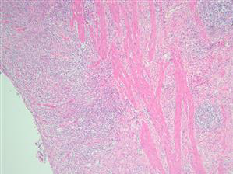

图5 术后病理镜下所见

术后病理(图5)示:(化疗后远端胃癌根治标本)黏膜慢性中度炎,大量急慢性炎细胞浸润,纤维组织增生,肉芽组织增生,未见明确癌组织残留,符合化疗后肿瘤完全退缩改变;自检(胃小弯侧)淋巴结18枚,(胃大弯侧)淋巴结13枚,均未见癌转移。(化疗后评分:Becker分级Grade 1a级,TRG评分0分)。